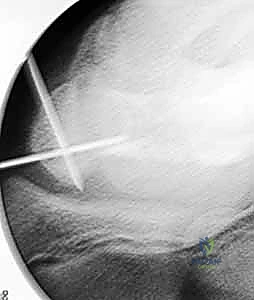

هذه هي التقنية المتقدمة التي يبرع فيها الأستاذ الدكتور محمد هطيف في صنعاء. بدلاً من فتح الرسغ، يتم إجراء العملية بأكملها من خلال شقوق دقيقة لا تتجاوز 2-3 مليمترات، تحت إرشاد جهاز الأشعة المرئية (Fluoroscopy) وبمساعدة المنظار المفصلي الدقيق.

العملية الجراحية بتقنية التدخل المحدود ليست مجرد "إدخال مسمار"، بل هي عمل فني وهندسي دقيق يتطلب مهارة جراحية فائقة، تخطيطاً مسبقاً، وتنسيقاً مثالياً بين يدي الجراح والصور الإشعاعية. يتبع الأستاذ الدكتور محمد هطيف بروتوكولاً صارماً لضمان أعلى معدلات النجاح.